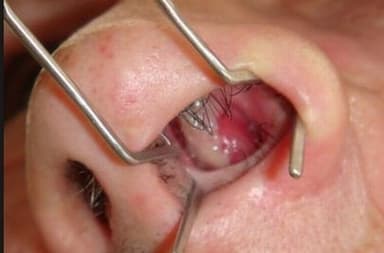

Polyp mũi ở trẻ nhỏ là khái niệm khá xa lạ đối với nhiều bậc phụ huynh. Đây được xem là 1 dạng khối u nhỏ nằm trong khoang mũi của trẻ, không gây đau đớn nhưng mang lại cảm giác khó chịu, vướng mắc, khó thở cho trẻ. Kèm theo đó là những triệu chứng như sổ mũi, sụt sịt, ho và viêm phế quản.

Polyp mũi được hình thành khi lớp niêm mạc mũi hoặc xoang bị viêm nhiễm, làm cho các mạch máu trong niêm mạc ứ đọng nước. Theo thời gian, các mô tế bào này bị nước bên trong kéo nặng xuống, tạo thành các khối tròn, mọc thành chùm nho.

– Phẫu thuật cắt bỏ polyp: Đây là phương pháp được chỉ định trong trường hợp polyp phát triển to, gây khó chịu, khó thở cho trẻ. Bác sĩ sẽ phẫu thuật khoang mũi hoặc các xoang mũi để loại bỏ polyp.

Phẫu thuật polyp mũi trong trường hợp polyp quá to, chiếm hết không gian xoang mũi